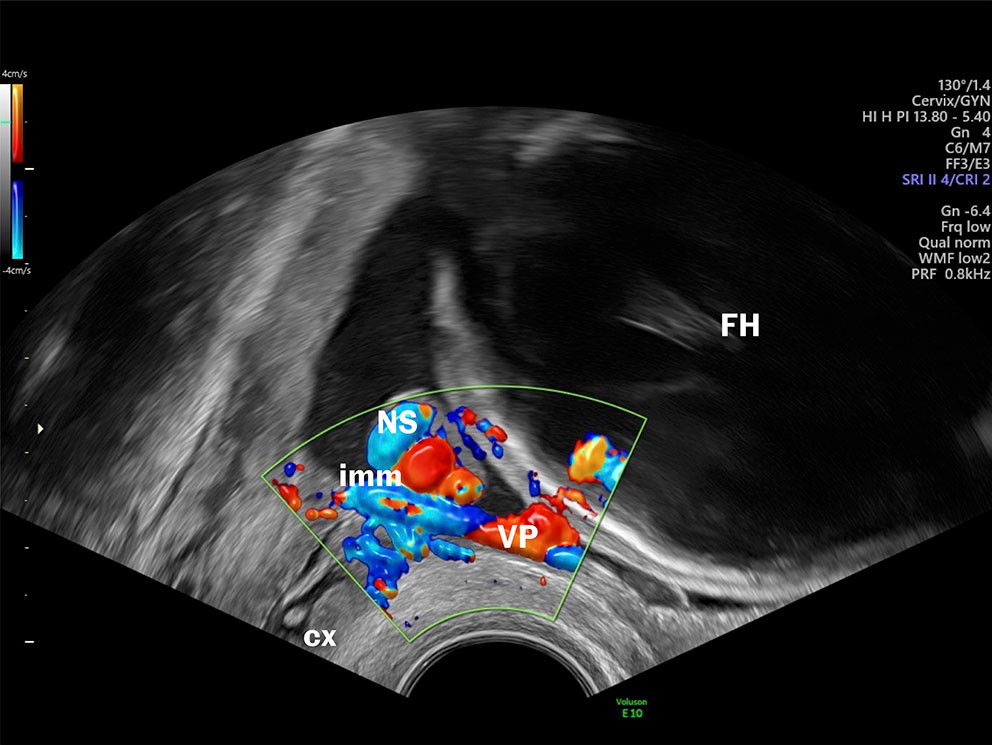

Antall blodårer i navlesnoren og morkakens plassering inngår allerede i rutineultralydundersøkelsen. Internasjonalt anbefales også at snorens feste til morkaken undersøkes (4). Bakgrunnen for at morkake og navlesnor skal undersøkes med ultralyd, er at man kan identifisere varianter som er assosiert med risiko, for eksempel der morkaken ligger foran indre mormunn (placenta previa) eller unormalt antall blodårer i navlesnoren. Ved velamentøse kar er de føtale blodårene ikke beskyttet av navlesnor eller morkake og er derfor sårbare for trykk og traume.

Velamentøse blodårer er assosiert med risiko for uønskede utfall for både mor og barn (5–8). I noen prosent av tilfellene løper de ubeskyttede føtale blodårene i hinnene foran indre mormunn. Da kalles tilstanden vasa previa. Når vasa previa er diagnostisert, er målet å forløse kvinnen med keisersnitt før spontan vannavgang eller ruptur av hinnene. Foster til termin har et blodvolum på ca. 3–4 dL (110 ml/kg) og det har ikke gode kompensasjonsmekanismer hvis det oppstår blødning. I løpet av sekunder kan blødning fra et velamentøst kar nå et volum som får fatale konsekvenser (9). Ikke uventet er derfor dødeligheten ved uerkjent vasa previa høy, opptil 56 %, og om barnet overlever, er det høy risiko for alvorlig sykelighet (10). Men dersom tilstanden er kjent før fødsel, er overlevelsen nesten 100 % og med normale utfall på kort og lengre sikt (11).

Selv om man har kjent til muligheten for å diagnostisere vasa previa og velamentøse blodårer med ultralyd siden sent på 1980-tallet, inngår det ikke å avkrefte eller bekrefte vasa previa i rutineundersøkelsen i Norge. Transvaginal ultralyd har høy sensitivitet og spesifisitet med hensyn til å diagnostisere vasa previa (13), og falskt positive og falskt negative funn forekommer sjelden. I tillegg er undersøkelsen billig, medfører lite ubehag for kvinnen, ingen risiko for fosteret og er rask å utføre (få minutter) (figur 1) (se video).